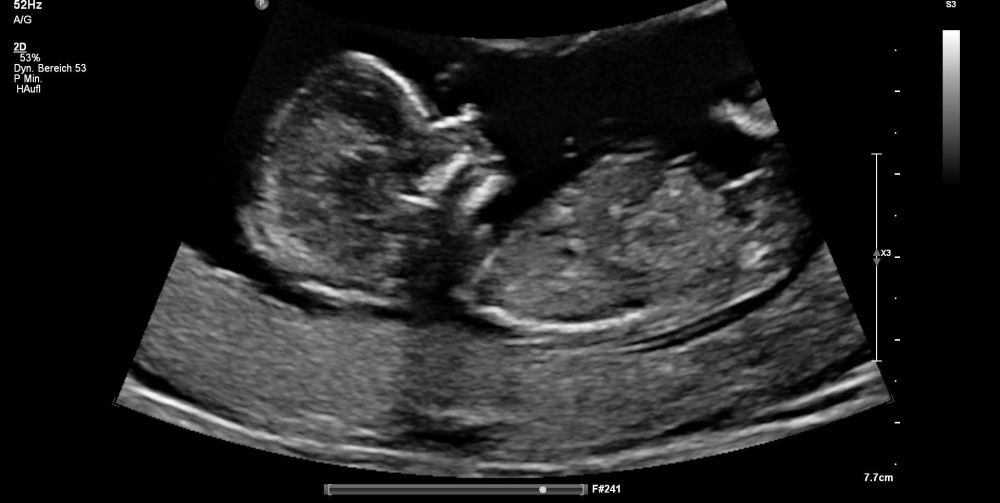

Hallo zusammen,

Ich hatte am Freitag einen Termin bei meiner Frauenärztin. Sie wollte sich bezüglich des Geschlechtes noch nicht festlegen. Was meint ihr?

Ich bin der 14 SSW.

Vielen lieben Dank